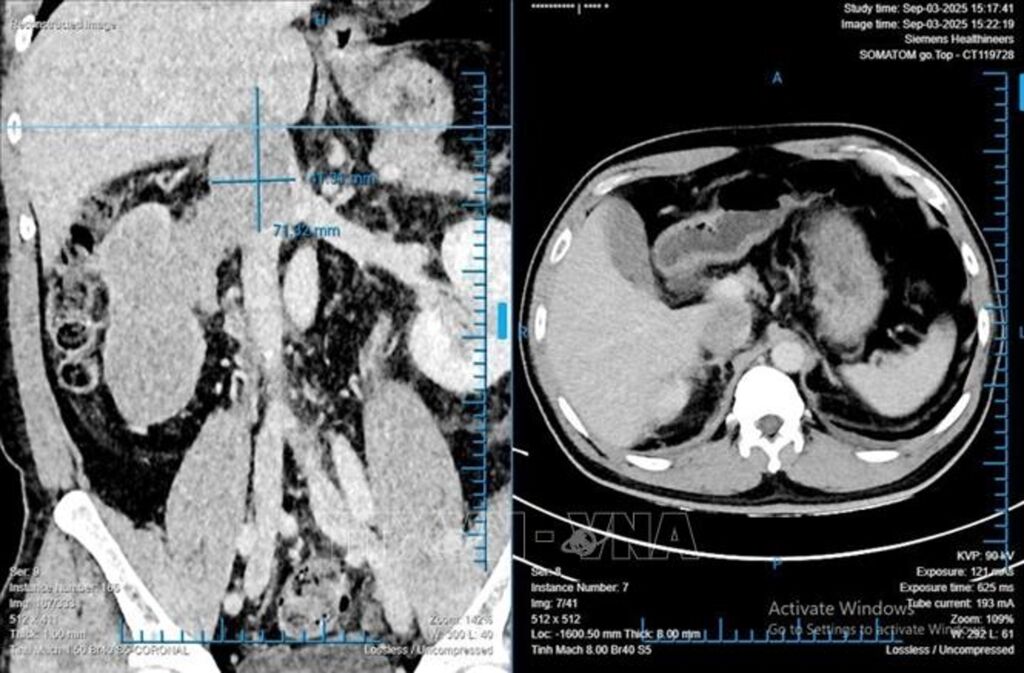

Trước đó, anh T.D.L (48 tuổi, quê Quảng Trị) phát hiện bướu thận trong lần khám sức khỏe định kỳ và tìm đến Bệnh viện Bình Dân để thực hiện phẫu thuật. Qua chẩn đoán hình ảnh, các bác sĩ nhận thấy bệnh nhân có một khối bướu lớn chiếm gần toàn bộ thận phải, kích thước 68x86x138 mm; huyết khối bướu lan sâu vào tĩnh mạch thận và tĩnh mạch chủ dưới. “Với khối bướu lớn và huyết khối bướu lan sâu như thế này, bệnh nhân có nguy cơ tử vong, tiên lượng thời gian sống trung bình của người bệnh chỉ khoảng 5 tháng nếu không được phẫu thuật kịp thời”, Tiến sĩ, bác sĩ Phạm Phú Phát, Trưởng Khoa Niệu A, Bệnh viện Bình Dân cho biết.

Theo Tiến sĩ, bác sĩ Phạm Phú Phát, đây là trường hợp ung thư biểu mô tế bào thận (RCC) có huyết khối bướu lên đến 76 mm, lớn nhất trong số các trường hợp mà các bác sĩ từng phẫu thuật. Một báo cáo tại Hoa Kỳ cũng ghi nhận chiều dài huyết khối bướu lớn nhất mà họ thực hiện là hơn 70 mm.